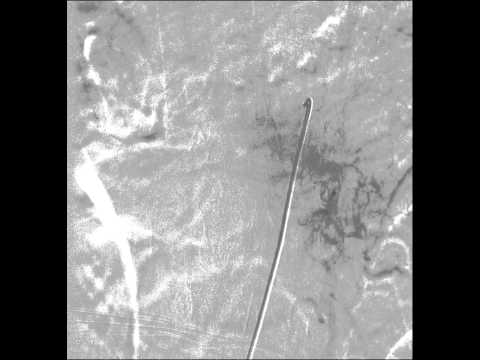

Spinal Dural AVF embolization